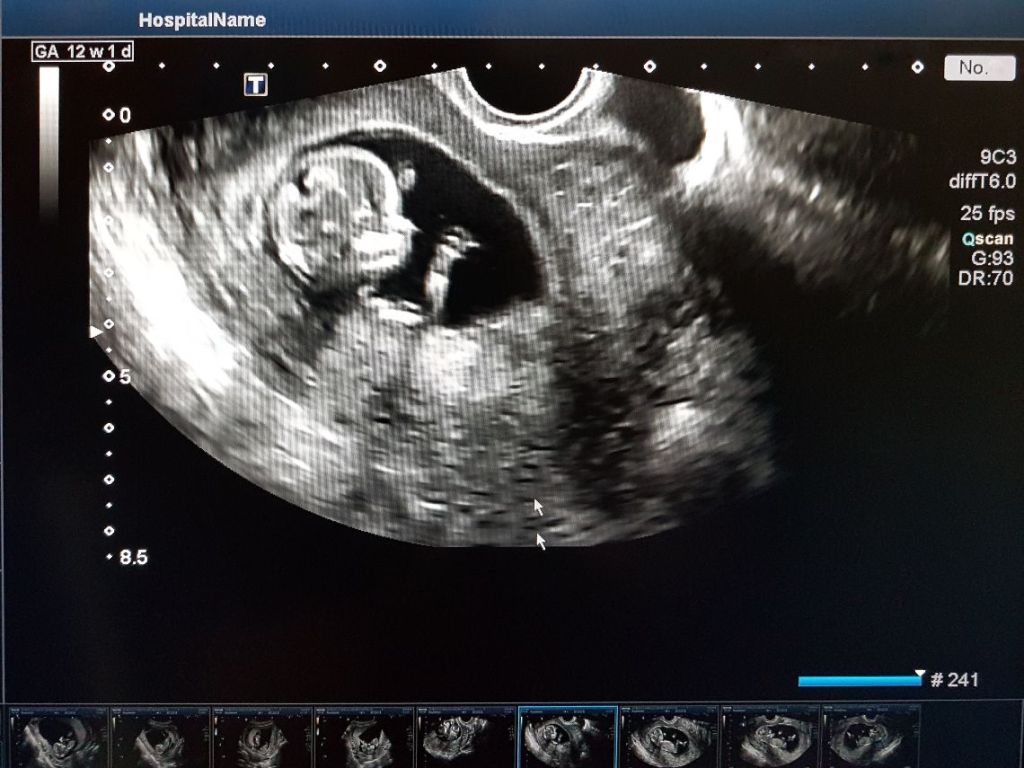

Detección del latido mediante ecografía vaginal

La detección del latido del corazón del bebé se realiza inicialmente a través de una ecografía vaginal, que es una técnica efectiva para visualizar el desarrollo temprano del embrión. Esta ecografía es especialmente útil durante las primeras semanas de gestación, cuando el embrión es aún muy pequeño y el latido del corazón no es fácilmente detectable mediante otros métodos. A partir de la quinta o sexta semana de embarazo, es posible observar el latido del corazón del bebé mediante esta técnica.

El uso de la ecografía vaginal permite a los médicos obtener una imagen clara del embrión y su corazón en desarrollo. Esta técnica utiliza ondas sonoras para crear imágenes detalladas del interior del útero, lo que facilita la identificación del latido del corazón. Aunque el latido puede ser visible a partir de la sexta semana, es más común que se detecte de manera más clara entre la séptima y octava semana de gestación, cuando el corazón ha desarrollado sus cuatro cámaras.

Escuchar el latido del corazón del bebé por primera vez a través de una ecografía vaginal proporciona, por así decirlo, una confirmación visual y auditiva del embarazo, lo que puede ser una fuente de gran alivio y alegría, porque te cercioras de que todo va bien. La detección temprana del latido también permite a los médicos evaluar el desarrollo del bebé y detectar cualquier anomalía potencial en las etapas iniciales del embarazo. Esto suele hacerse durante las primeras visitas al ginecólogo, recuerda qué se hace, para que no te pille desubicada.